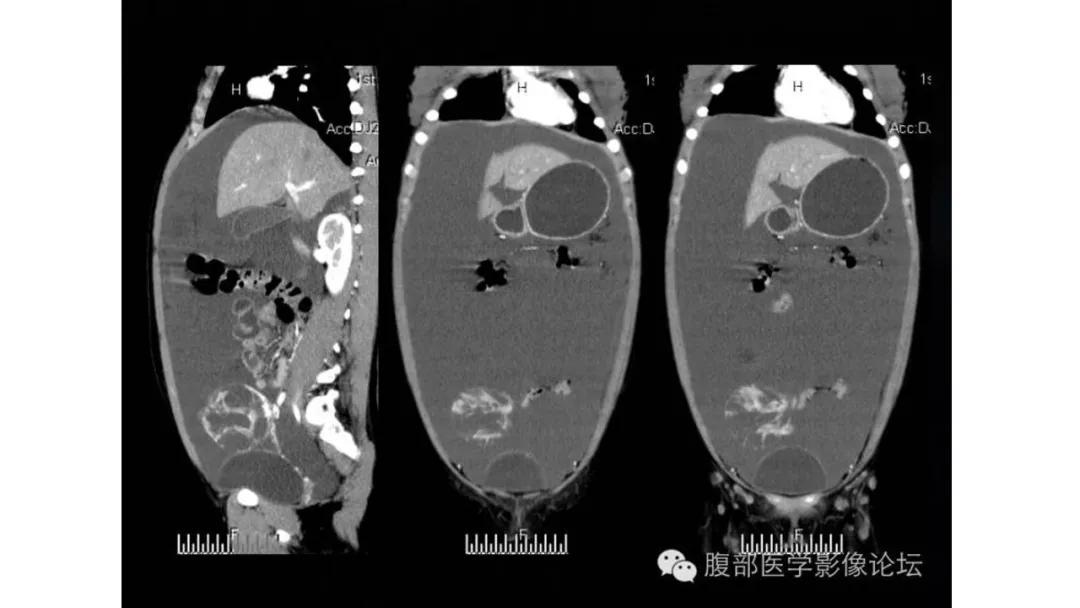

病理:颗粒细胞瘤